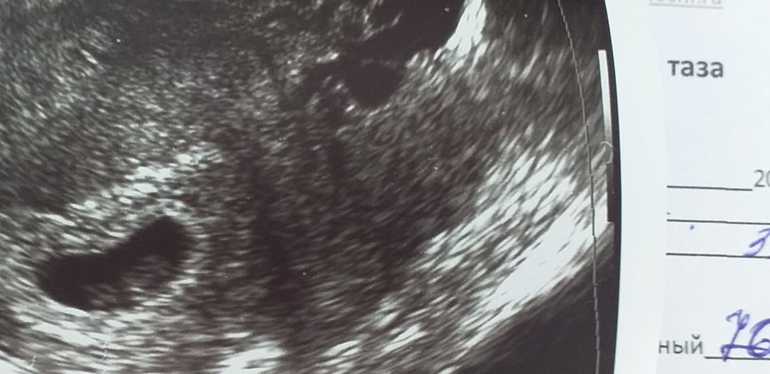

Ходила сегодня, 30.12, на узи. Нашли нашего малышастика, развивается по нормам и по сроку!

6 недель. ПЯ 20, ЖМ 3.8, Ктр 4.8, сердцебиение + (не включали чтобы не беспокоить)